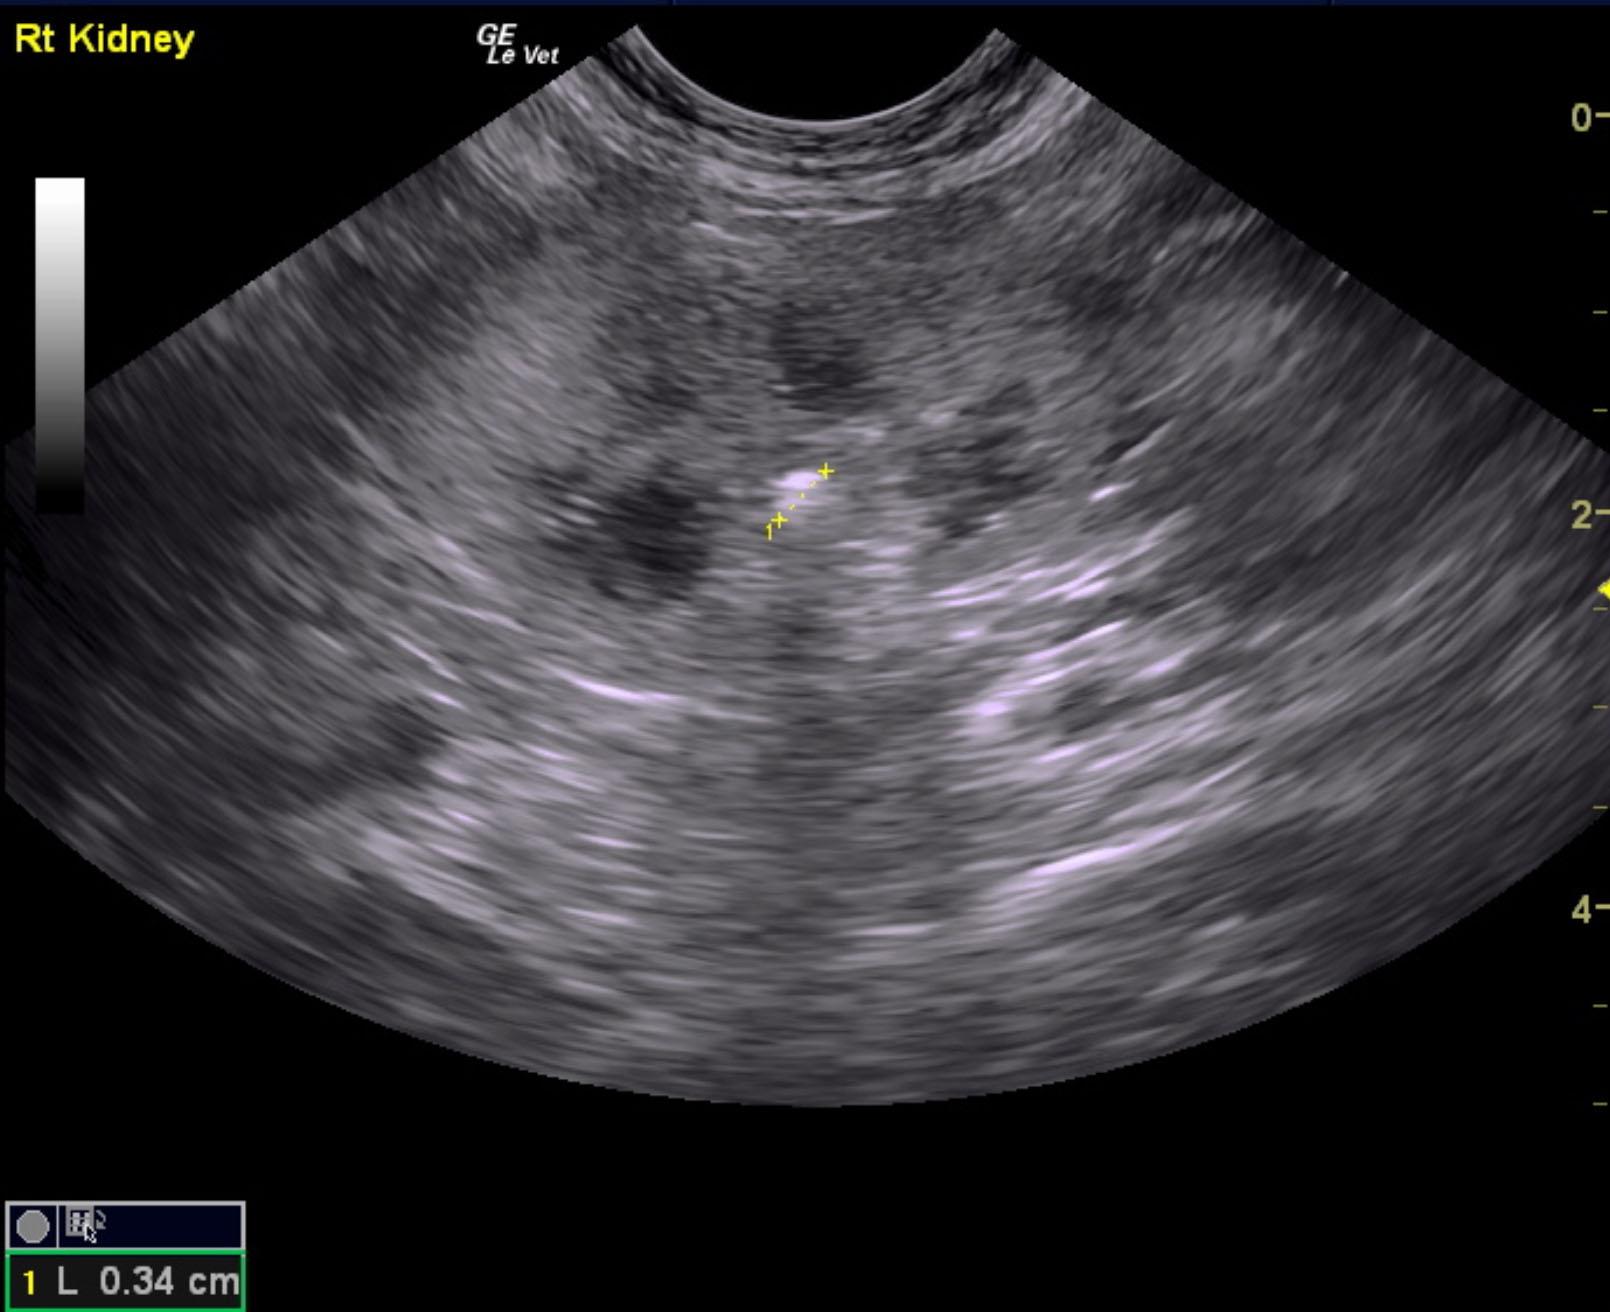

A 5-year-old NM DSH was presented for evaluation of weight loss and a 5-day history of decreased appetite and lethargy. On physical examination 8% dehydration, pale mucosa, and a full but easily expressible bladder were present. Abnormalities on CBC and serum biochemistry were mild lymphopenia and neutrophilia, azotemia (BUN >180, creatinine >20), and hypoproteinemia. Survey radiographs showed irregular kidneys with opacities and possible opacities within the urethra.